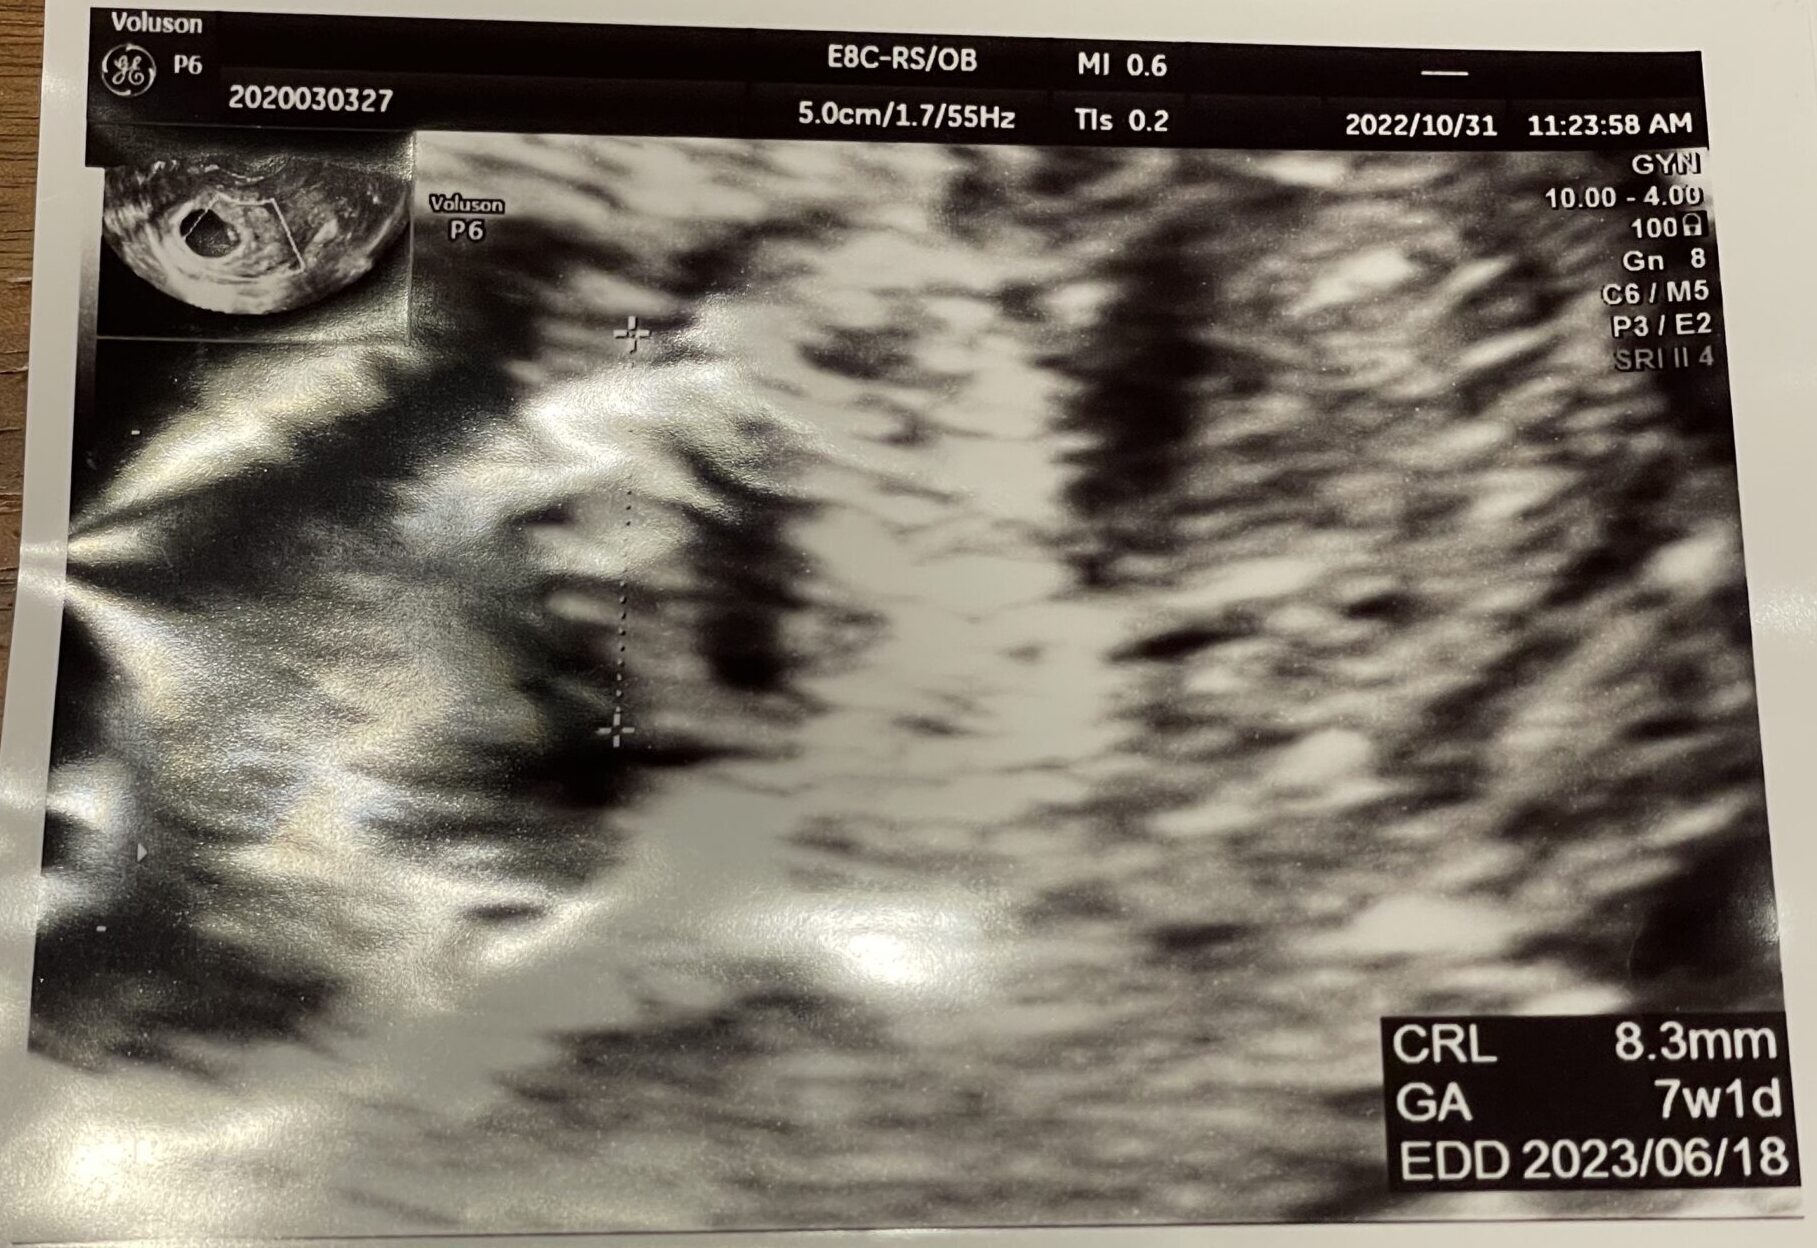

昨日で7週、妊娠2ヶ月にあたります。

チカチカひかる、赤ちゃんの心臓。

その後、経膣エコーでしっかりと赤ちゃんの姿を見せてくれました…!クリオネみたい!

初めて見たわが子は、胎嚢のすみっこで縮こまっているように見えて、すごく愛おしく思えました。

8.3mmの小さな赤ちゃんの心臓がチカチカチカチカ…と一生懸命動いていて、第1子のときにもすごく印象的だった場面。その頃の気持ちも少し蘇ってきました。心拍確認って大事なことだなぁ。